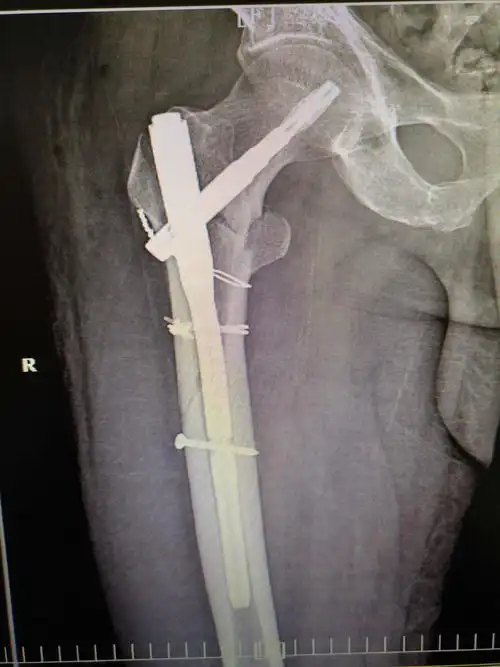

股骨干骨折闭合复位髓内钉内固定手术一例

股骨干合并股骨颈骨折一例

小儿股骨骨折1例

岳阳市长炼医院外一科一例股骨骨折病例分享

钛缆 pfna治疗老年股骨近端粉碎性骨折

股骨干骨折